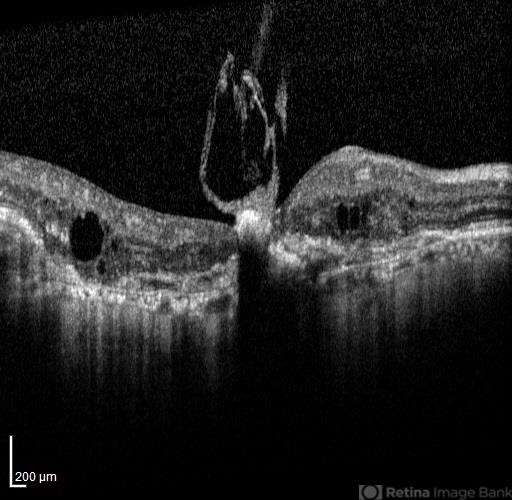

- optical coherence tomography (OCT), age-related macular degeneration (AMD), vitreomacular adhesion

- Nayereh Hadipour, Negah Eye Center, Tehran, Iran

Optical coherence tomography system

Specteralis - Description

- OCT of the right eye of a 75-year-old man with advanced wet type AMD.